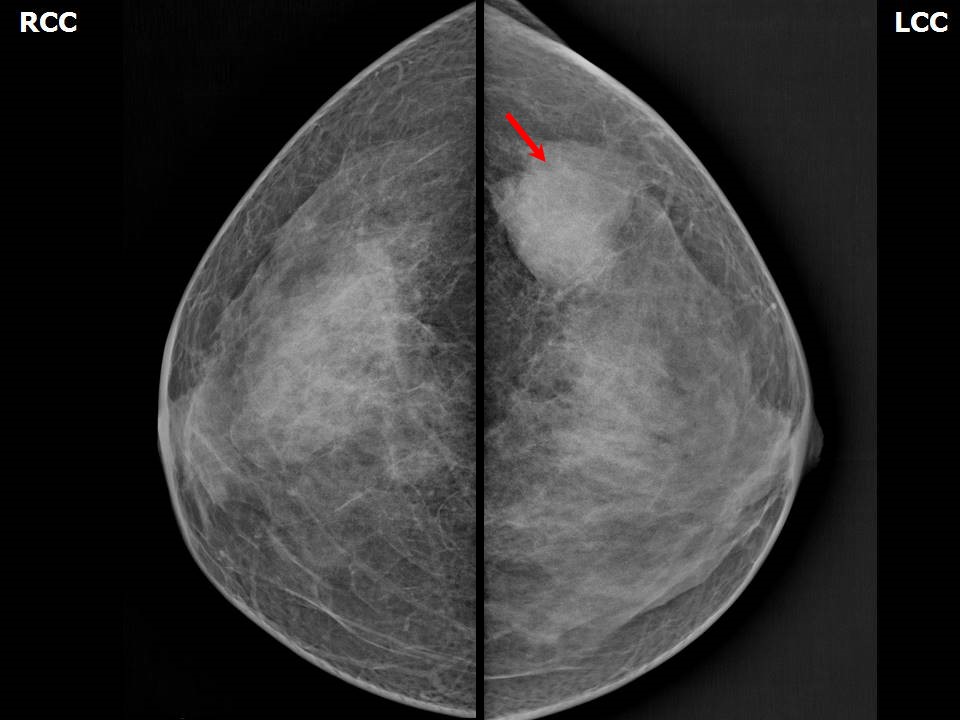

Феномен гипердиагностики в маммографии: примеры и иллюстрации

Раздел: Образы вокруг